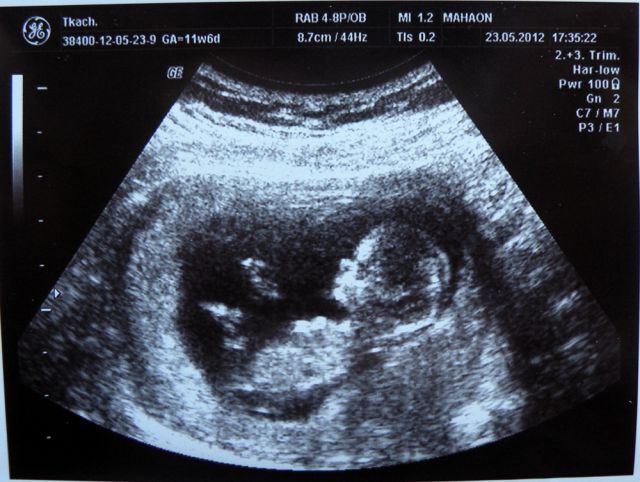

در حدود هفته یازده, رویان به طور رسمی جنین شناخته می شود. به طور مشخص خصوصیات چهره و دستگاه تناسلی جنین در حال رشد ونمو است و سونوگرافی هفته یازدهم می تواند چشم اندازی دقیق از نحوه رشد را به شما نمایش دهد. پس سونوگرافی تعیین جنسیت از هفته ۱۱ انجام می شود.

سونوگرافی سه ماهه اول به دلیل دید کلی که از رشد جنین می دهد بسیار مهم است. این سونوگرافی که به سونوگرافی ان تی نیز معروف است از هفته ۱۱-۱۴ بارداری انجام می شود. با سونوگرافی هفته یازدهم می توان برای اولین بار چهره فرزند خود را برانداز کنید. این سونوگرافی همچنین اولین سونوگرافی برای تشخیص قطعی ناهنجاری هاست.

جنین در هفته 11, با دستان و پاهای کامل شکل گرفته , بیشتر به انسان شبیه می شود. سر و استخوان های جنین در این مرحله شکل گرفته است. جنین هنوز با سر بزرگ و تنه کوچک ظاهری نامتناسب دارد.

اندازه جنین در این مرحله 2.5 تا 5 سانتی متر است اما رشد ارگان ها بسیار سریع است.